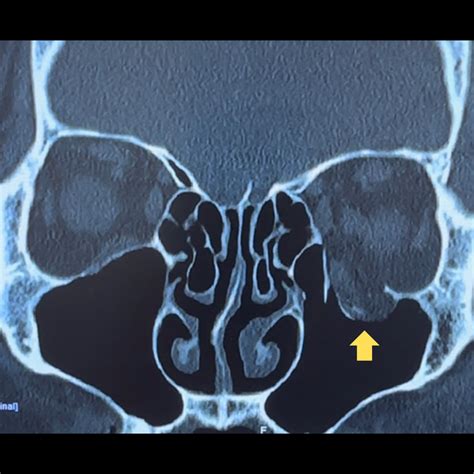

The symptoms of an orbital fracture can vary significantly depending on the location and severity of the break. Some fractures may be hairline cracks, while others are “blow-out” fractures, where the force causes the thin orbital floor to collapse into the underlying sinus cavity. It is crucial to monitor for the following signs following facial trauma:

2. Imaging Studies: A CT scan (Computed Tomography) is the gold standard for diagnosing orbital fractures. It provides a detailed, 3D view of the orbital bones and surrounding tissues, which is essential for determining if surgery is required.